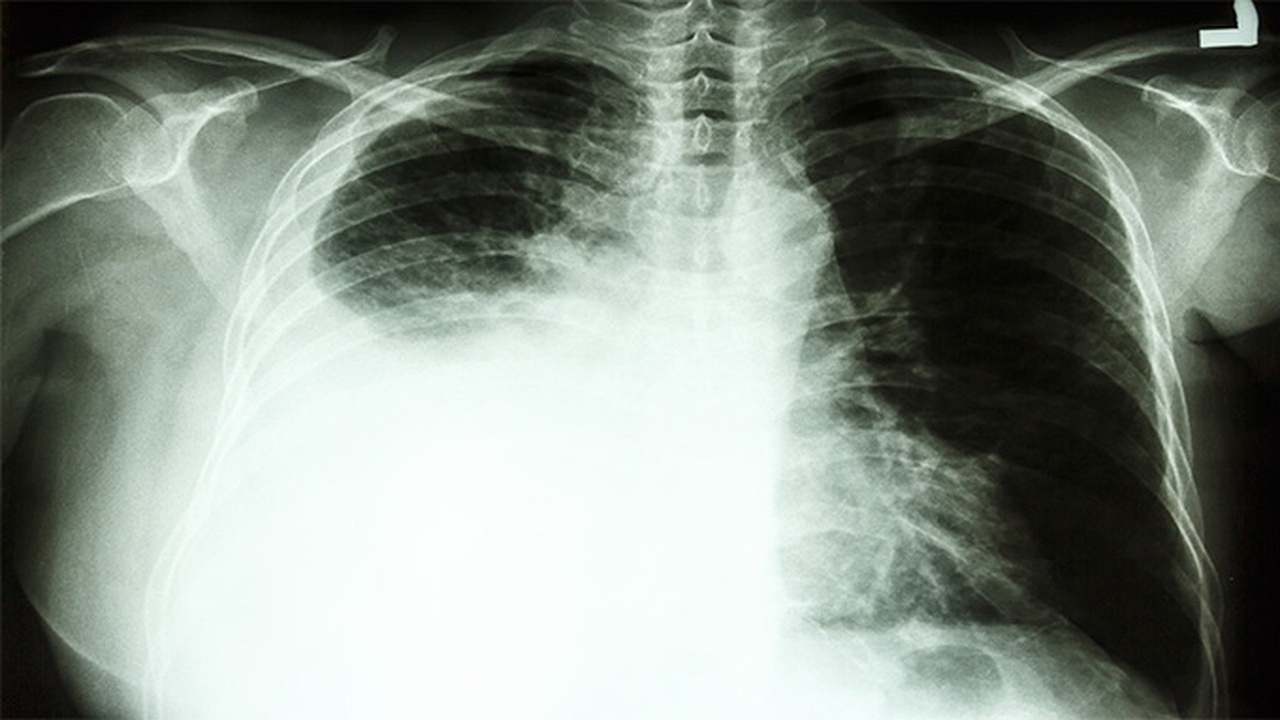

肺癌的发病原因复杂多样,长期吸烟是主要诱因,此外空气污染、职业暴露、遗传因素等也可能增加患病风险。早期诊断和规范化治疗对提高生存率至关重要。